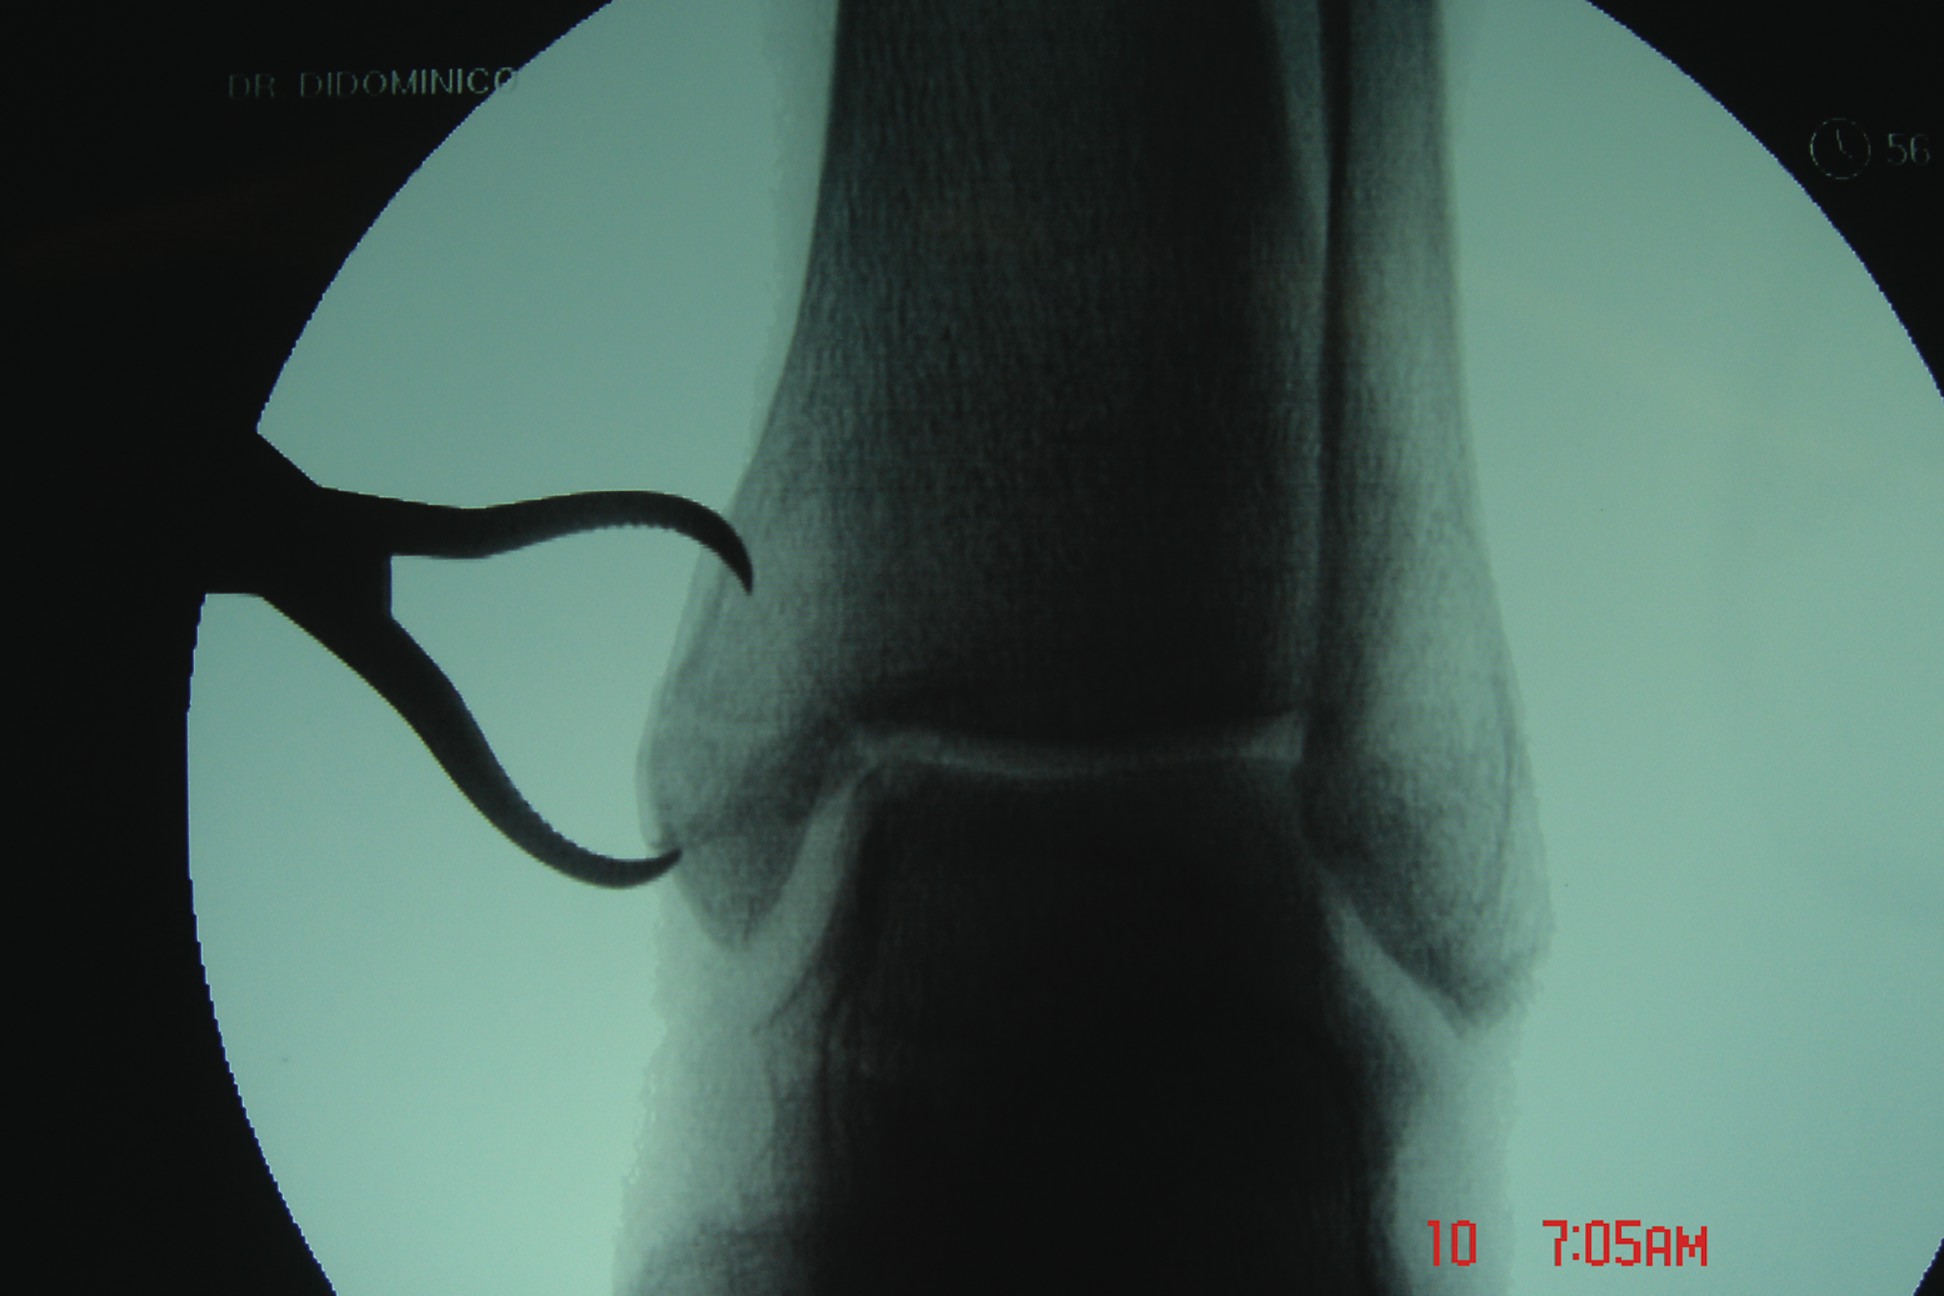

The Lauge-Hansen classification system is the most widely used system to assess ankle fractures.6 This system helps the physician visualize the mechanism of injury, the ability to reproduce the fracture, ascertain the anatomy involved and ability to reduce the fracture. (See “What You Should Know About The Lauge-Hansen Classification System” below.) This classification system was solely based on experimental cadaveric studies and clinical experiences with common fractures. The first term describes the position of the foot at the time of injury while the second term describes the direction of the pathologic force on the talus. The staging in this classification is as follows: supination-adduction, supination-eversion (supination–external rotation), pronation-abduction, pronation-eversion (pronation-external rotation).6 The Danis-Weber classification system is the second commonly utilized system among surgeons when it comes to identifying the degree of ankle fractures. However, the use of this system has increased in recent years due to the ease of classifying the fracture. The basis of this system is classified on the fracture pattern of the fibula and the integrity of the syndesmosis. This classification recognizes Type A, Type B and Type C fractures.6 With a Type A fracture, the fracture line is below the ankle joint level. These fractures account for 14.8 to 27 percent of all ankle fractures. Approximately 41 percent of ankle fractures are Type B fractures, in which the fracture line is at the level of the ankle joint. Type C fractures, which involve a fracture line below the level of the ankle joint, comprise about 20 percent of ankle fractures. The Berndt and Harty classification is the most commonly accepted system clinicians use for describing transchondral lesions. The defect often results from a shearing of the distal tibia and talar dome under compression that is often secondary to an ankle sprain or fracture. These types of injuries are difficult to recognize in acute phase due to the similar presentation of an ankle sprain. According to the Berndt and Harty classification, a stage 1 lesion is a trabecular compression fracture of subchondral bone; a stage 2 lesion is a partially detached osteochondral fragment; a stage 3 lesion involves a completely detached, non-displaced fragment; and a stage 4 lesion involves a detached and displaced fragment. In regard to assessing the degree of epiphyseal fractures in pediatric patients, the classification system proposed by Salter and Harris is the most widely accepted (see “A Closer Look At The Salter-Harris Classification System For Epiphyseal Fractures” below). The mean age for most physeal fractures is reportedly in the range of 1 to 16 years old with 10 years of age being the average.

All athletes, regardless of the level of performance, will need the appropriate physical therapy modalities and rehabilitative techniques to complete functional recovery from an ankle fracture. Athletes who are at the competitive amateur level or professional level will need to return to their performance level sooner than the weekend warrior. Athletes whose career is based on their performance and return to competition will need complete rehabilitation. These individuals have no financial constraints as compared to some amateur athletes and recreational athletes. There are three phases of rehabilitation: the acute phase, the recovery phase and the functional phase. Phase one is the reduction of pain, inflammation and edema while retarding muscle atrophy of the lower extremity complex. Improving range of motion is also a major component in this acute phase. Phase two involves improving range of motion, improving lower extremity strength, increasing neuromuscular control and regaining normal arthrokinematics (defined as function of the joint) in single planes and triplanar motion of the ankle. Phase three involves increasing power of the lower extremity complex, increasing neuromuscular control in multiple planes of motion and utilizing sport-specific training for a full return to sport.30,31 A consideration with treating athletes is that if the athlete is inactive after his or her injury, the athlete loses training adaptation. This means the athlete will “detrain” as the individual’s physiological function reverts to the normal untrained state.32 It is most essential that the athlete remain active in some form of alternative exercise or maintenance program during the rehabilitative period in order to maintain his or her mental and physical strength. Alternative activities include water running and weight training of the upper extremity and the noninvolved lower extremity. Any form of maintaining aerobic capacity, neuromuscular coordination and muscle strength will help reduce injury.30 When it comes to ankle fractures in competitive athletes who require full function of their joints and motion, these individuals will need complete reduction with no malalignment. In previous studies, authors have shown that 1 to 2 mm of displacement of the fibula can cause an increase in tibiotalar contact up to 42 percent. This can lead to increased arthrosis and pain, which can reduce the longevity of playing careers.33 The trend is to perform open reduction and internal fixation of the fracture for early mobilization/rehabilitation, especially when it comes to early season injuries and reducing recovery time in order to facilitate a return to mid-season or end of the season play.7 If an injury occurs at the end of the season, the goal is getting an athlete fully rehabilitated for offseason training. If the podiatrist manages the athlete surgically with open reduction and internal fixation, one may have the patient begin early partial weightbearing in a walking boot with passive range of motion exercises at one to two weeks postoperatively. If you are treating professional athletes or high level college athletes, one may utilize bone stimulation in the postoperative management regimen to increase healing time. The athlete can begin physical therapy at two weeks postoperatively with phase one of rehabilitation exercises. The first phase of rehabilitation will include passive range of motion exercises and cryotherapy, which clinicians can initiate immediately after surgery by having the patient wear circulating cryotherapy boots at the hospital or surgery center. After the patient has met the goals of the first phase of rehabilitation, one may proceed to the second phase, which is usually initiated at three to four weeks postoperatively. One must remember to use pain as a guide in dealing with any type of rehabilitation procedure. In the second phase, patients may initiate strengthening with Theraband, range of motion exercises and proprioception exercises with a biomechanical ankle platform system (BAPS). Advise these patients that when they use theraband, they should use the least resistant bands initially. Toward the end of the second phase, the athlete should begin using a wobble board to improve proprioception and begin closed kinetic chain activities such as walking and loading. In the sixth to eighth week post-op, the athlete should begin the third phase of rehabilitation, which involves improving power, increasing neuromuscular control and utilizing sport-specific training of the lower extremity for a full return to sport.31 In the functional phase of rehabilitation, one may initiate plyometric (defined as “used to restore force”) exercises such as double-leg jumping, single leg jumping, four-square hopping, use of a minitramp and running to cutting progressions.30,31 The athlete should continue neuromuscular exercises and leg control exercises in this phase as well. The hip and leg control exercises involve hip and knee strengthening, one-legged stance and agility drills. Sport-specific exercises involving jumping, cutting and kicking offer a final component to the rehabilitation process.31 In regard to the various physical therapy modalities, such as iontophoresis, ultrasound, contrast bathing and interferential stimulation, one should continue utilizing these modalities to reduce swelling, pain and improve motion. Protecting the injured extremity will be very important in the later stages of rehabilitation with taping and bracing. When the athlete returns to full speed activity, he or she should continue to utilize a supportive device indefinitely.

There are some controversies in regard to the postoperative management of ankle fractures. One controversy is whether to begin early partial weightbearing versus non-weightbearing. The standard postoperative management advised by the Association for the Study of Internal Fixation after the internal fixation of ankle fractures is the use of crutches without weightbearing. The majority of literature supports early range of motion and protected weightbearing after anatomical reduction with stable internal fixation. In previous prospective randomized studies on early weightbearing and mobilization of surgically stabilized ankle fractures, Ahl, et. al., found that early active ankle movements with the addition of weightbearing improve rehabilitation following the surgical repair of ankle fractures.25-29 His series of studies also showed an improvement in ankle dorsiflexion and plantarflexion of the operated ankle at three and six months postoperatively with early mobilization and weightbearing. Other benefits of early weightbearing and mobilization include a reduction of stiffness, swelling, muscle atrophy and disuse osteopenia. Once you have decided how to treat the patient, then you can decide when to begin rehabilitation.